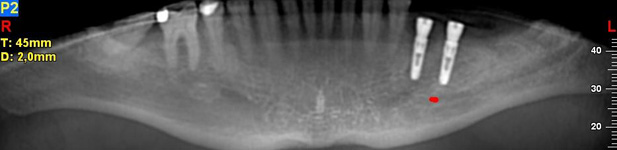

Lékař si vytvoří všechny typy zobrazení potřebných pro naplánování – tedy 2D snímky (panoramatický), příčné řezy i 3D model.

Vidí zde i důležité anatomické útvary – čelistní dutinu, průběh nervu atd. Po proměření množství kosti – šířky i výšky vybere z databáze vhodný typ implantátu a umístí ho do požadované lokality.

Ihned vidí jeho pozici ve všech 3 rovinách a na všech snímcích i 3D modelu. Může upravovat podle potřeby jeho pozici, sklon atd.

Vidí zde i důležité anatomické útvary – čelistní dutinu, průběh nervu atd. Po proměření množství kosti – šířky i výšky vybere z databáze vhodný typ implantátu a umístí ho do požadované lokality. Ihned vidí jeho pozici ve všech 3 rovinách a na

všech snímcích i 3D modelu. Může upravovat podle potřeby jeho pozici, sklon atd.